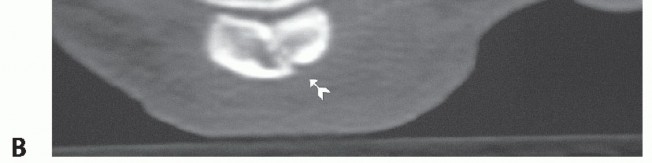

Sesamoid oblique and tangential (“skyline”) views are useful to evaluate sesamoid fracture displacement (FIG 4A).

A longitudinal computed tomography (CT) scan of the foot has been shown to be very effective in demonstrating sesamoid stress fracture in difficult settings4 (FIG 4B).

FIG 4 • Radiologic examination of sesamoid fractures. A. Conventional radiographs demonstrating horizontal sesamoid fracture dislocation. B. CT scan shows fracture line of chronic painful sesamoid, which was not visible on conventional radiographs.*